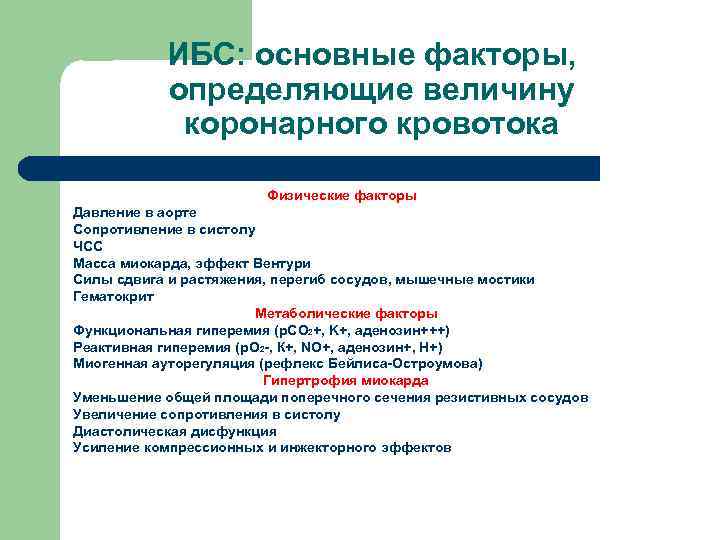

ИБС: основные факторы, определяющие величину коронарного кровотока l l l Физические факторы Метаболические факторы Нейрогуморальные факторы Реакция на ишемию Гипертрофия миокарда

ИБС: основные факторы, определяющие величину коронарного кровотока Физические факторы Давление в аорте Сопротивление в систолу ЧСС Масса миокарда, эффект Вентури Силы сдвига и растяжения, перегиб сосудов, мышечные мостики Гематокрит Метаболические факторы Функциональная гиперемия (p. CO 2+, K+, аденозин+++) Реактивная гиперемия (р. О 2 -, К+, NO+, аденозин+, Н+) Миогенная ауторегуляция (рефлекс Бейлиса-Остроумова) Гипертрофия миокарда Уменьшение общей площади поперечного сечения резистивных сосудов Увеличение сопротивления в систолу Диастолическая дисфункция Усиление компрессионных и инжекторного эффектов